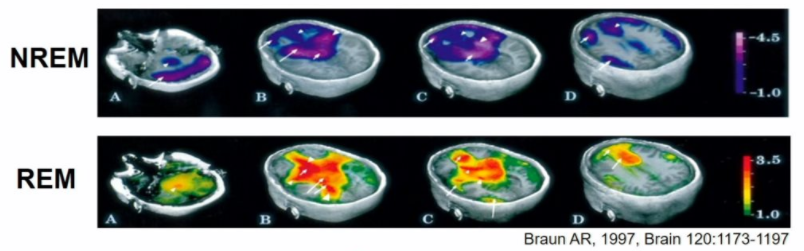

compared to SWS, REM involves increased blood flow in:

• pons, midbrain, basal gang

• paralimbic regions

• association cortices

A

paralimbic activity higher in REM than in awake brain